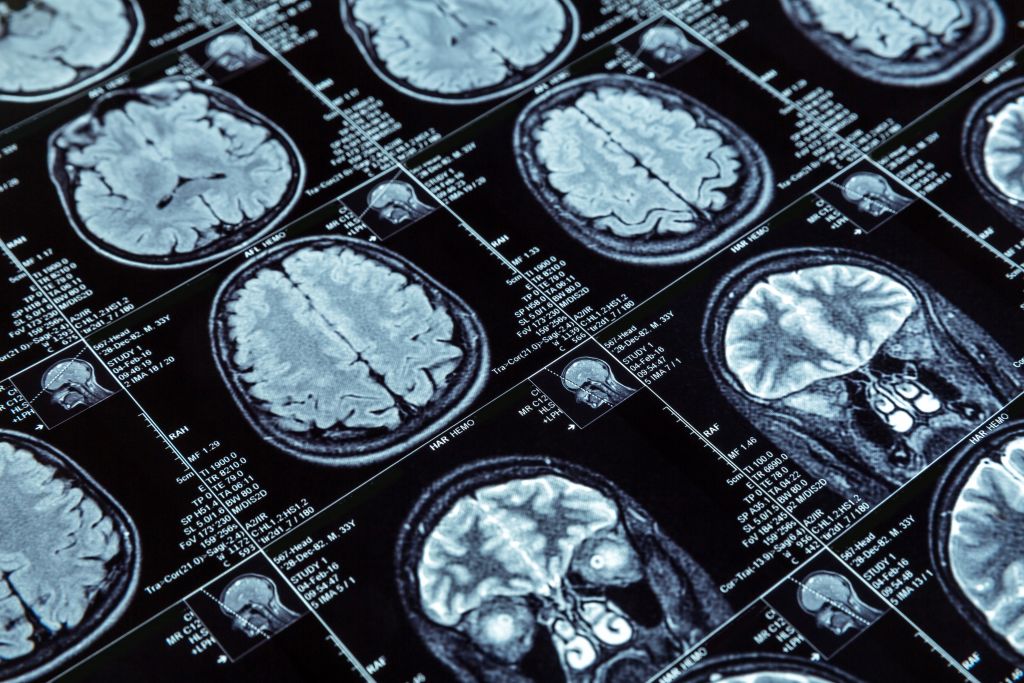

Ερευνητές στις ΗΠΑ, με επικεφαλής έναν Έλληνα επιστήμονα της διασποράς, αναπτύσσουν μια νέου τύπου θεραπεία για καρκίνους του εγκεφάλου, η οποία συνδυάζει νανοσωματίδια και εστιασμένους υπέρηχους, επιτρέποντας σε ισχυρά φάρμακα RNA να διαπεράσουν τον αιματοεγκεφαλικό φραγμό. Η θεραπεία δοκιμάστηκε με επιτυχία σε πειραματόζωα (τρωκτικά), ανοίγοντας το δρόμο για τη δοκιμή της σε ανθρώπους και αφήνοντας υποσχέσεις ότι μπορεί να αποτελέσει μελλοντικά μια νέα θεραπεία για τον καρκίνο του εγκεφάλου.

Το ριβονουκλεϊκό οξύ (RNA), το οποίο αποτελεί τη «ραχοκοκαλιά» των νέου τύπου εμβολίων που χρησιμοποιούνται κατά της νόσου Covid-19, θα μπορούσε, όπως δείχνει η νέα έρευνα, να χρησιμοποιηθεί και για τη θεραπεία εγκεφαλικών όγκων, οι οποίοι συχνά είναι ανθεκτικοί στη συνήθη χημειοθεραπεία και ακτινοθεραπεία. Οι ερευνητές διαπίστωσαν ότι ένας τύπος RNA, που ονομάζεται μικροπαρεμβαλλόμενος RNA ή siRNA, αν συσκευαστεί σε ειδικά νανοσωματίδια και συνδυαστεί με την τεχνική του «εστιασμένου υπέρηχου με μικροφυσαλίδες», μπορεί να διακόψει την έκφραση ορισμένων γονιδίων που οδηγούν σε καρκίνο.